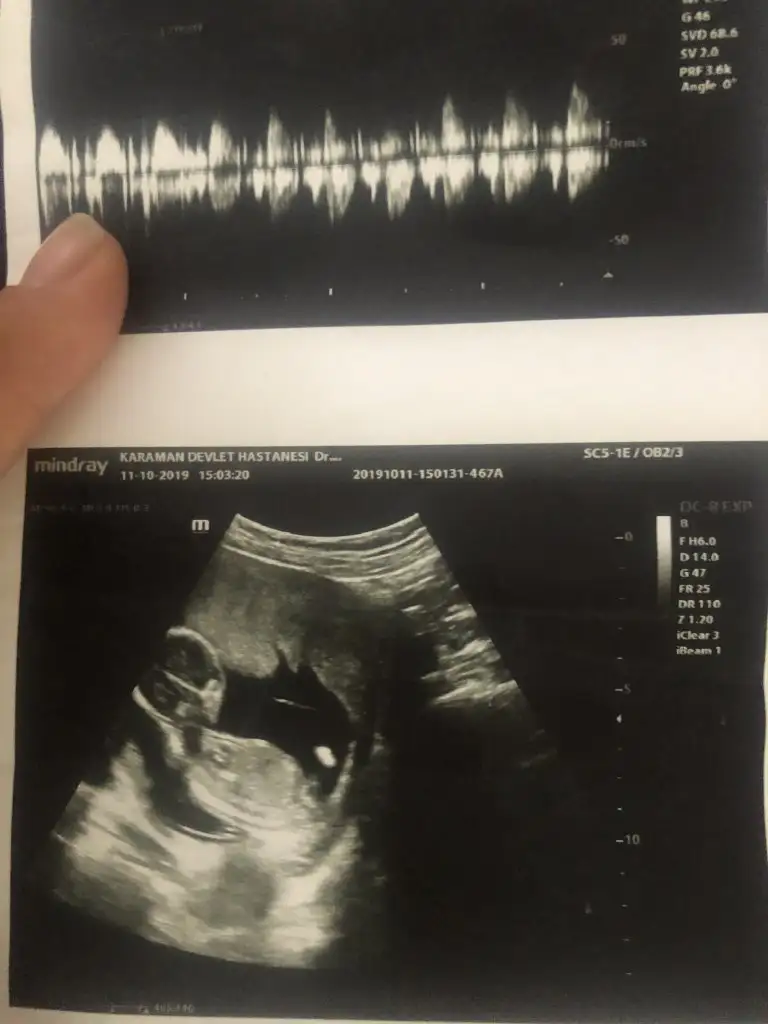

Bence de kız Canım direk usg ye baktım okumadan kız dedim doktor da aynısını demiş Allah bana da nasip ett inşallah böyle usgMerhabalar,bebeğim 12+5,doktorumuz kız dedi, mümkünse bende tahmin alabilir miyim

Erkek gibi geldi banaMerhabalar,bebeğim 12+5,doktorumuz kız dedi, mümkünse bende tahmin alabilir miyim